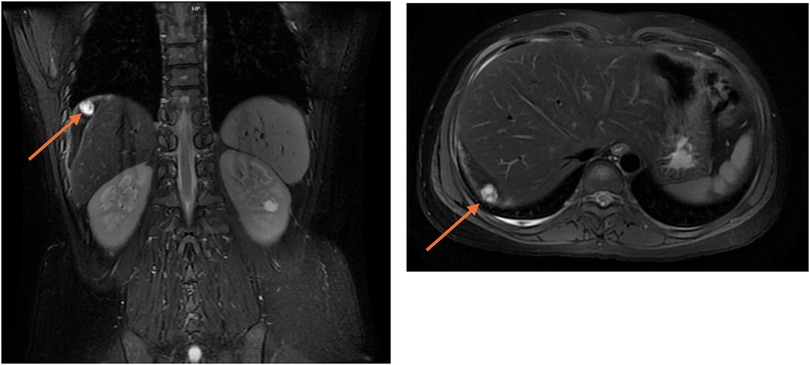

After the operation, the patient's right upper abdominal pain (Kehr's sign) alleviated slightly. On the second postoperative day, the patient's β-hCG level (5,400 mIU/mL) was higher than preoperative levels, indicating persistent ectopic pregnancy. Both the patient and their family were informed of the condition and expressed understanding. Conservative treatment involving an intramuscular injection of 80 mg of methotrexate (MTX) was administered. On the 4th postoperative day, the blood β-hCG level was 5,933 mIU/mL, and on the 5th postoperative day, the blood β-hCG level was 6,858 mIU/mL. This persistent rise suggested an inadequate response to MTX. The patient and their family were informed of this, and further examinations were arranged, including a pulmonary CT scan and a contrast-enhanced abdominal MRI scan. The lung CT scan revealed no abnormalities, eliminating the possibility of gestational trophoblastic disease. However, the abdominal enhanced MRI revealed that the size of the ectopic pregnancy tissue was approximately 1.6 cm at the outer edge of the right lobe of the liver, accompanied by peripheral clots, which was considered to be the tissue of the abdominal cavity pregnancy (Figure 1). The patient was in a stable condition, with no bloody drainage from the abdominal catheter, and slight relief of pain in the right upper abdominal pain. Following consultation with the patient and their family regarding further conservative or surgical treatment, they opted for conservative management initially. As MTX-based conservative treatment yielded suboptimal results, therapy was switched to intravenous mono-chemotherapy with 5-fluorouracil (5-FU) at a dose of 1.25 mg per day for 6 days. The blood β-hCG levels were rechecked every other day and decreased to 5,310 mIU/mL, 4,231 mIU/mL, and 1,886 mIU/mL, indicating a significant downward trend.

Figure 1. Abdominal MRI showed ectopic pregnancy tissue combined with hemorrhage visible in the periphery of the right lobe of the liver, with a maximum diameter of approximately 1.6 cm, as indicated by the arrow.